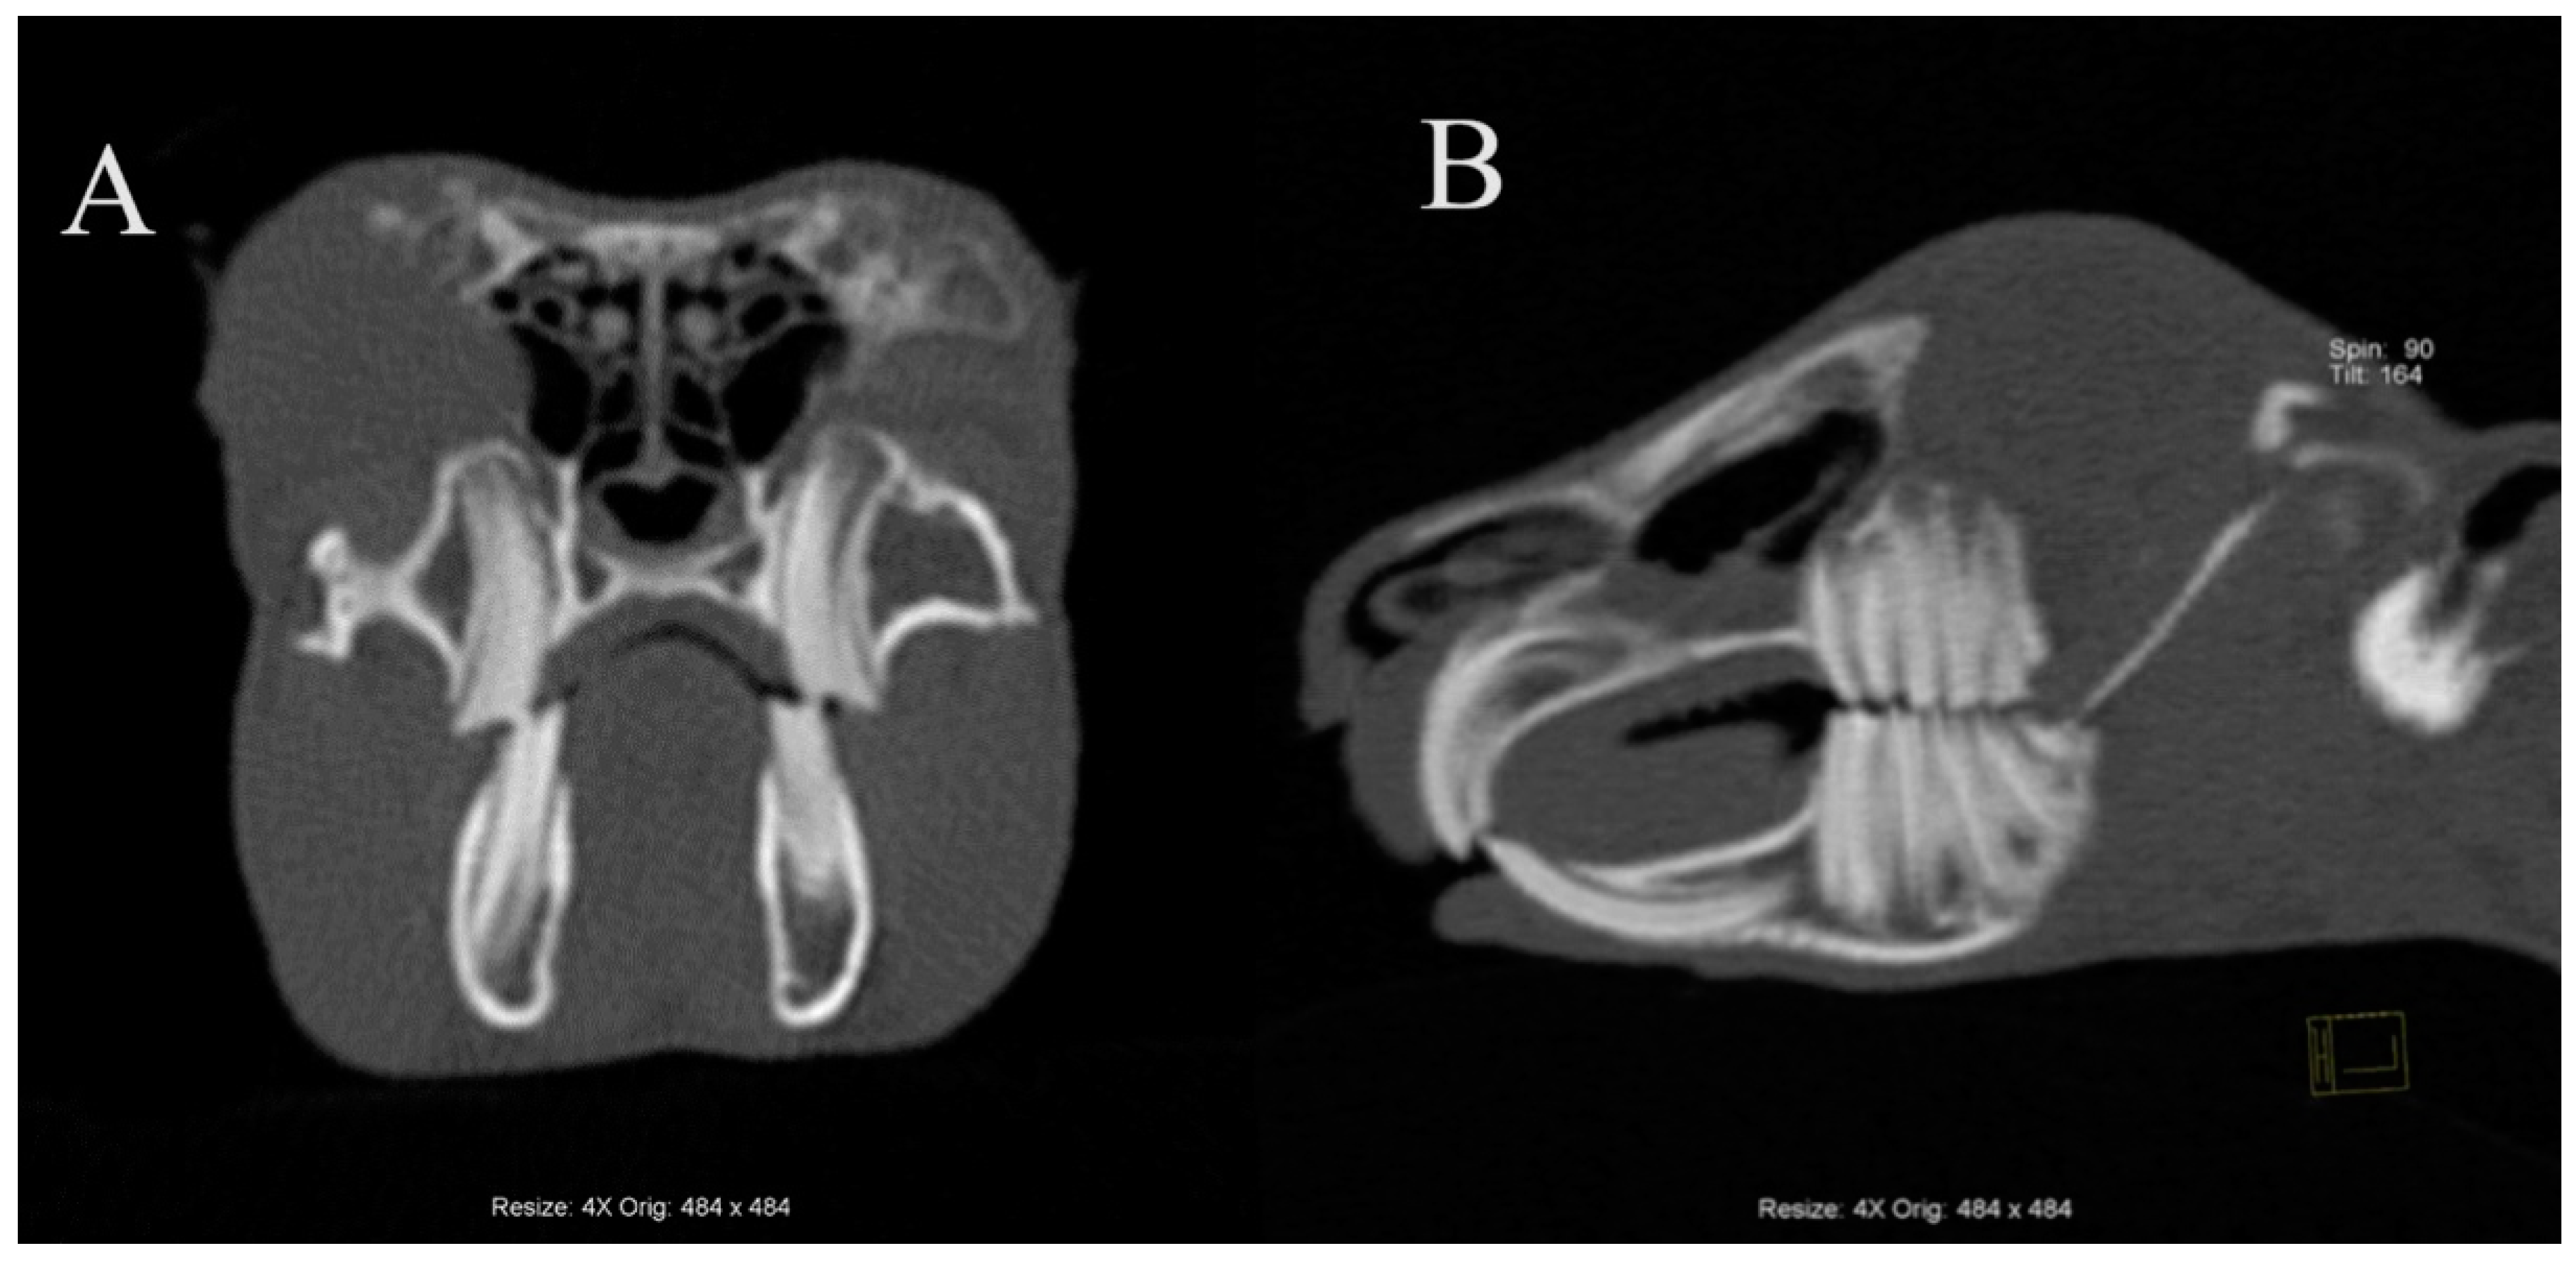

3.2. Prevalence of Retrograde Apical Elongation in the Mandible in Domestic Rabbits

3.3. Prevalence of Retrograde Apical Elongation in the Maxilla and Bone Deformities Secondary to It